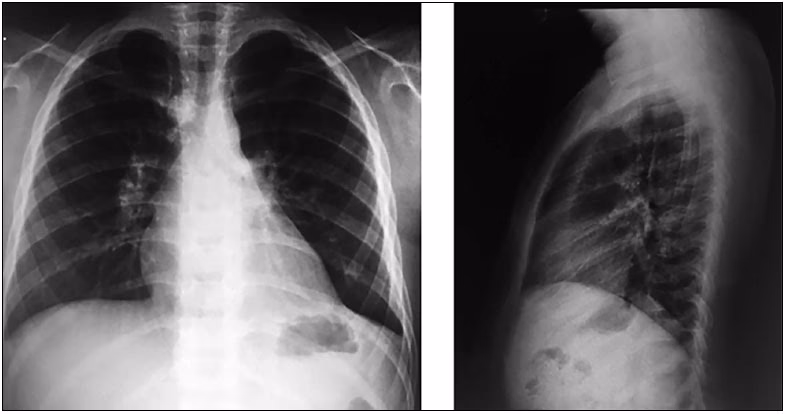

Diagnosen stilles af en læge baseret på en fysisk undersøgelse, hvor lægen lytter på barnets lunger med et stetoskop. Lægen vil også vurdere barnets vejrtrækningsfrekvens og generelle tilstand. I mange tilfælde vil et røntgenbillede af brystkassen være nødvendigt for at bekræfte diagnosen og se omfanget af infektionen. Blodprøver kan også tages for at identificere den specifikke virus eller bakterie.